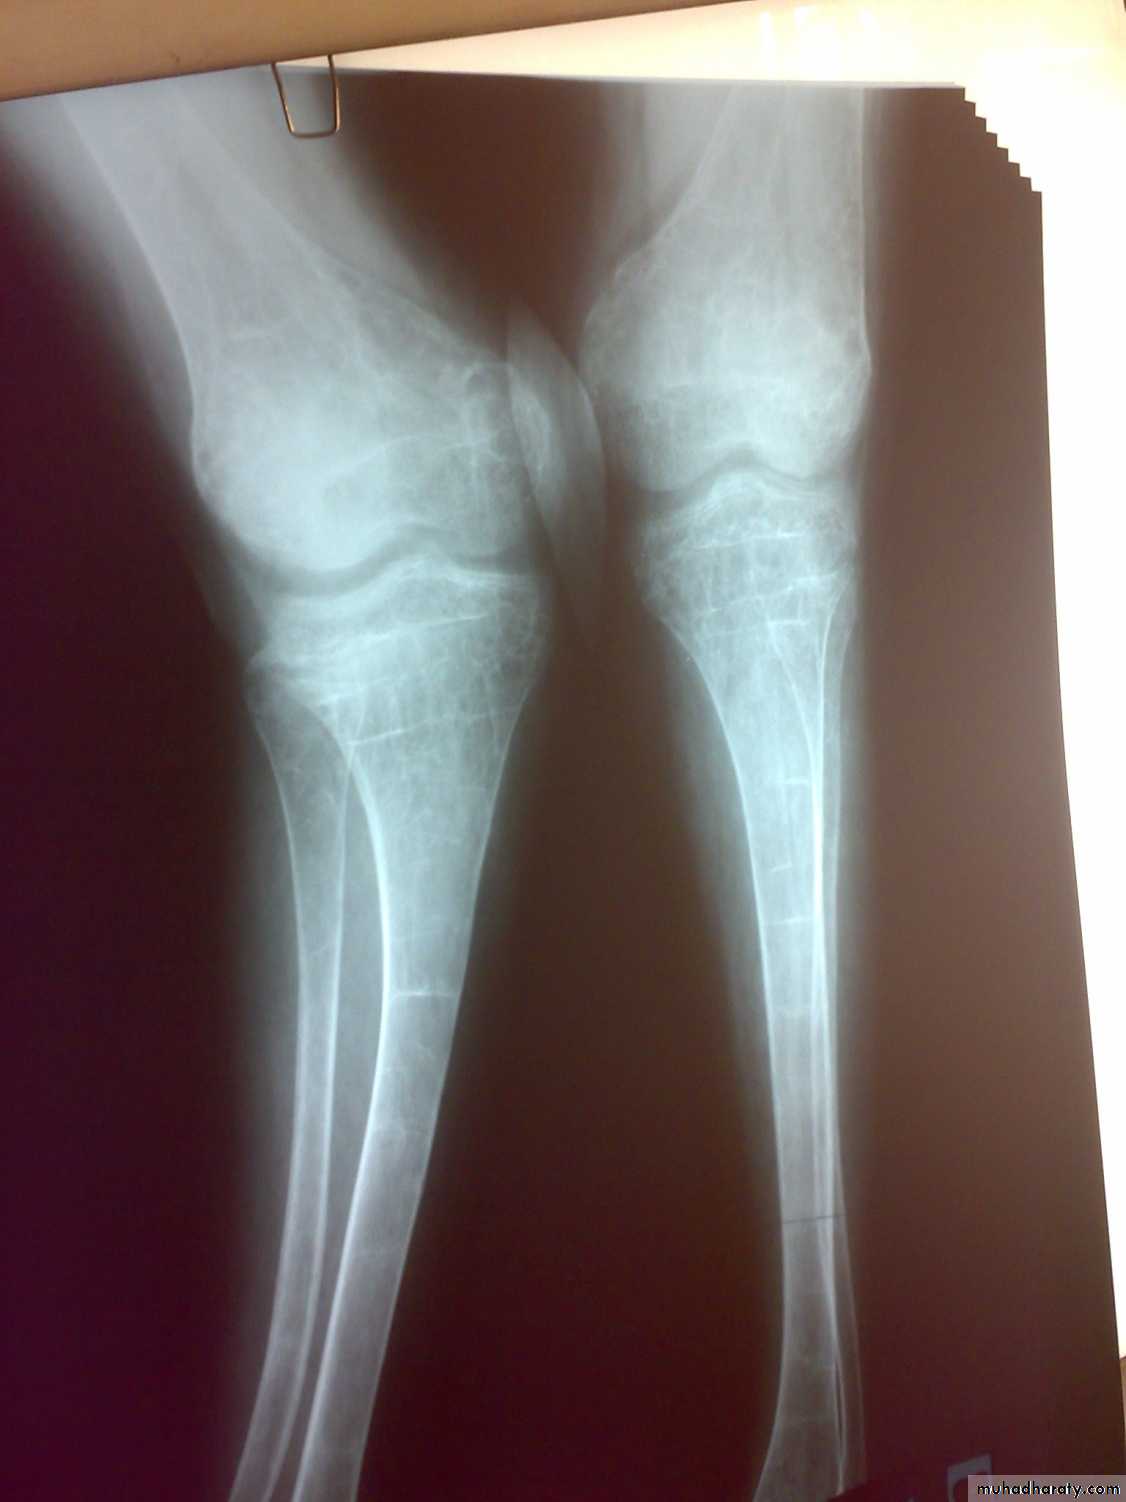

Osteomalacia and ricketsinadequate mineralization of bone

Bone tissue throughout the skeleton is abnormally calcified and therefore soften ( Osteomalacia).Rickets and Osteomalacia is same disease.

Losser’s zone

decreased serum phosphate

elevated serum alka. Phosphatase.

Ca × p< 2.4 mmol/ L